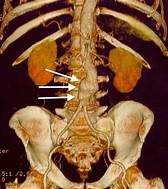

Acute renal failure is one of the possible complications of abdominal aortic aneurysm (AAA) repair, especially after open surgery. Acute renal failure is a sudden loss of kidney function that can cause fluid and electrolyte imbalance, acid-base disturbance, and uremic syndrome. Acute renal failure can occur due to several factors, such as hypoperfusion of the kidneys, atheroembolism, contrast- induced nephropathy, or ischemia-reperfusion injury.

The incidence of acute renal failure after AAA repair ranges from 2 to 25%, depending on the definition, the type of surgery, and the patient's risk factors.

Acute renal failure is associated with increased morbidity, mortality, and length of hospital stay after AAA repair.

Other complications of AAA repair include bleeding, infection, wound complications, graft-related complications, bowel ischemia, spinal cord ischemia, and cardiac, pulmonary, or neurological events.

Acute hepatic dysfunction, acute CVA, and atrial fibrillation are not specific complications of AAA repair, but they may occur in any major surgery or in patients with preexisting conditions.